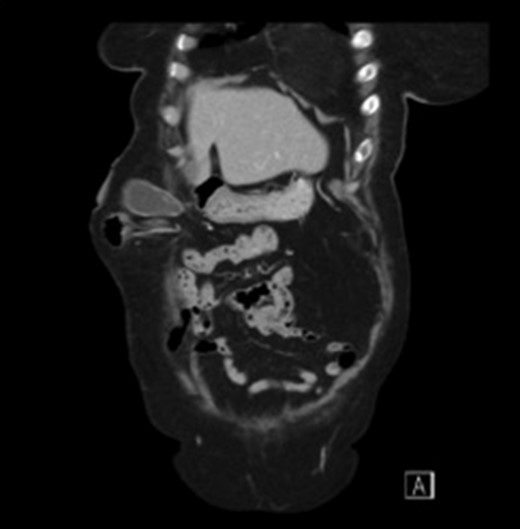

Subsequent Computed Tomography (CT) of the abdomen and pelvis revealed a parastomal hernia containing the gallbladder (Figs 1 and 2). There was no evidence of cholecysitis or choledocholithiasis. CBD was dilated to 9 mm without any filling defects.

Sagittal view CT scan of the gallbladder in the parastomal hernia.